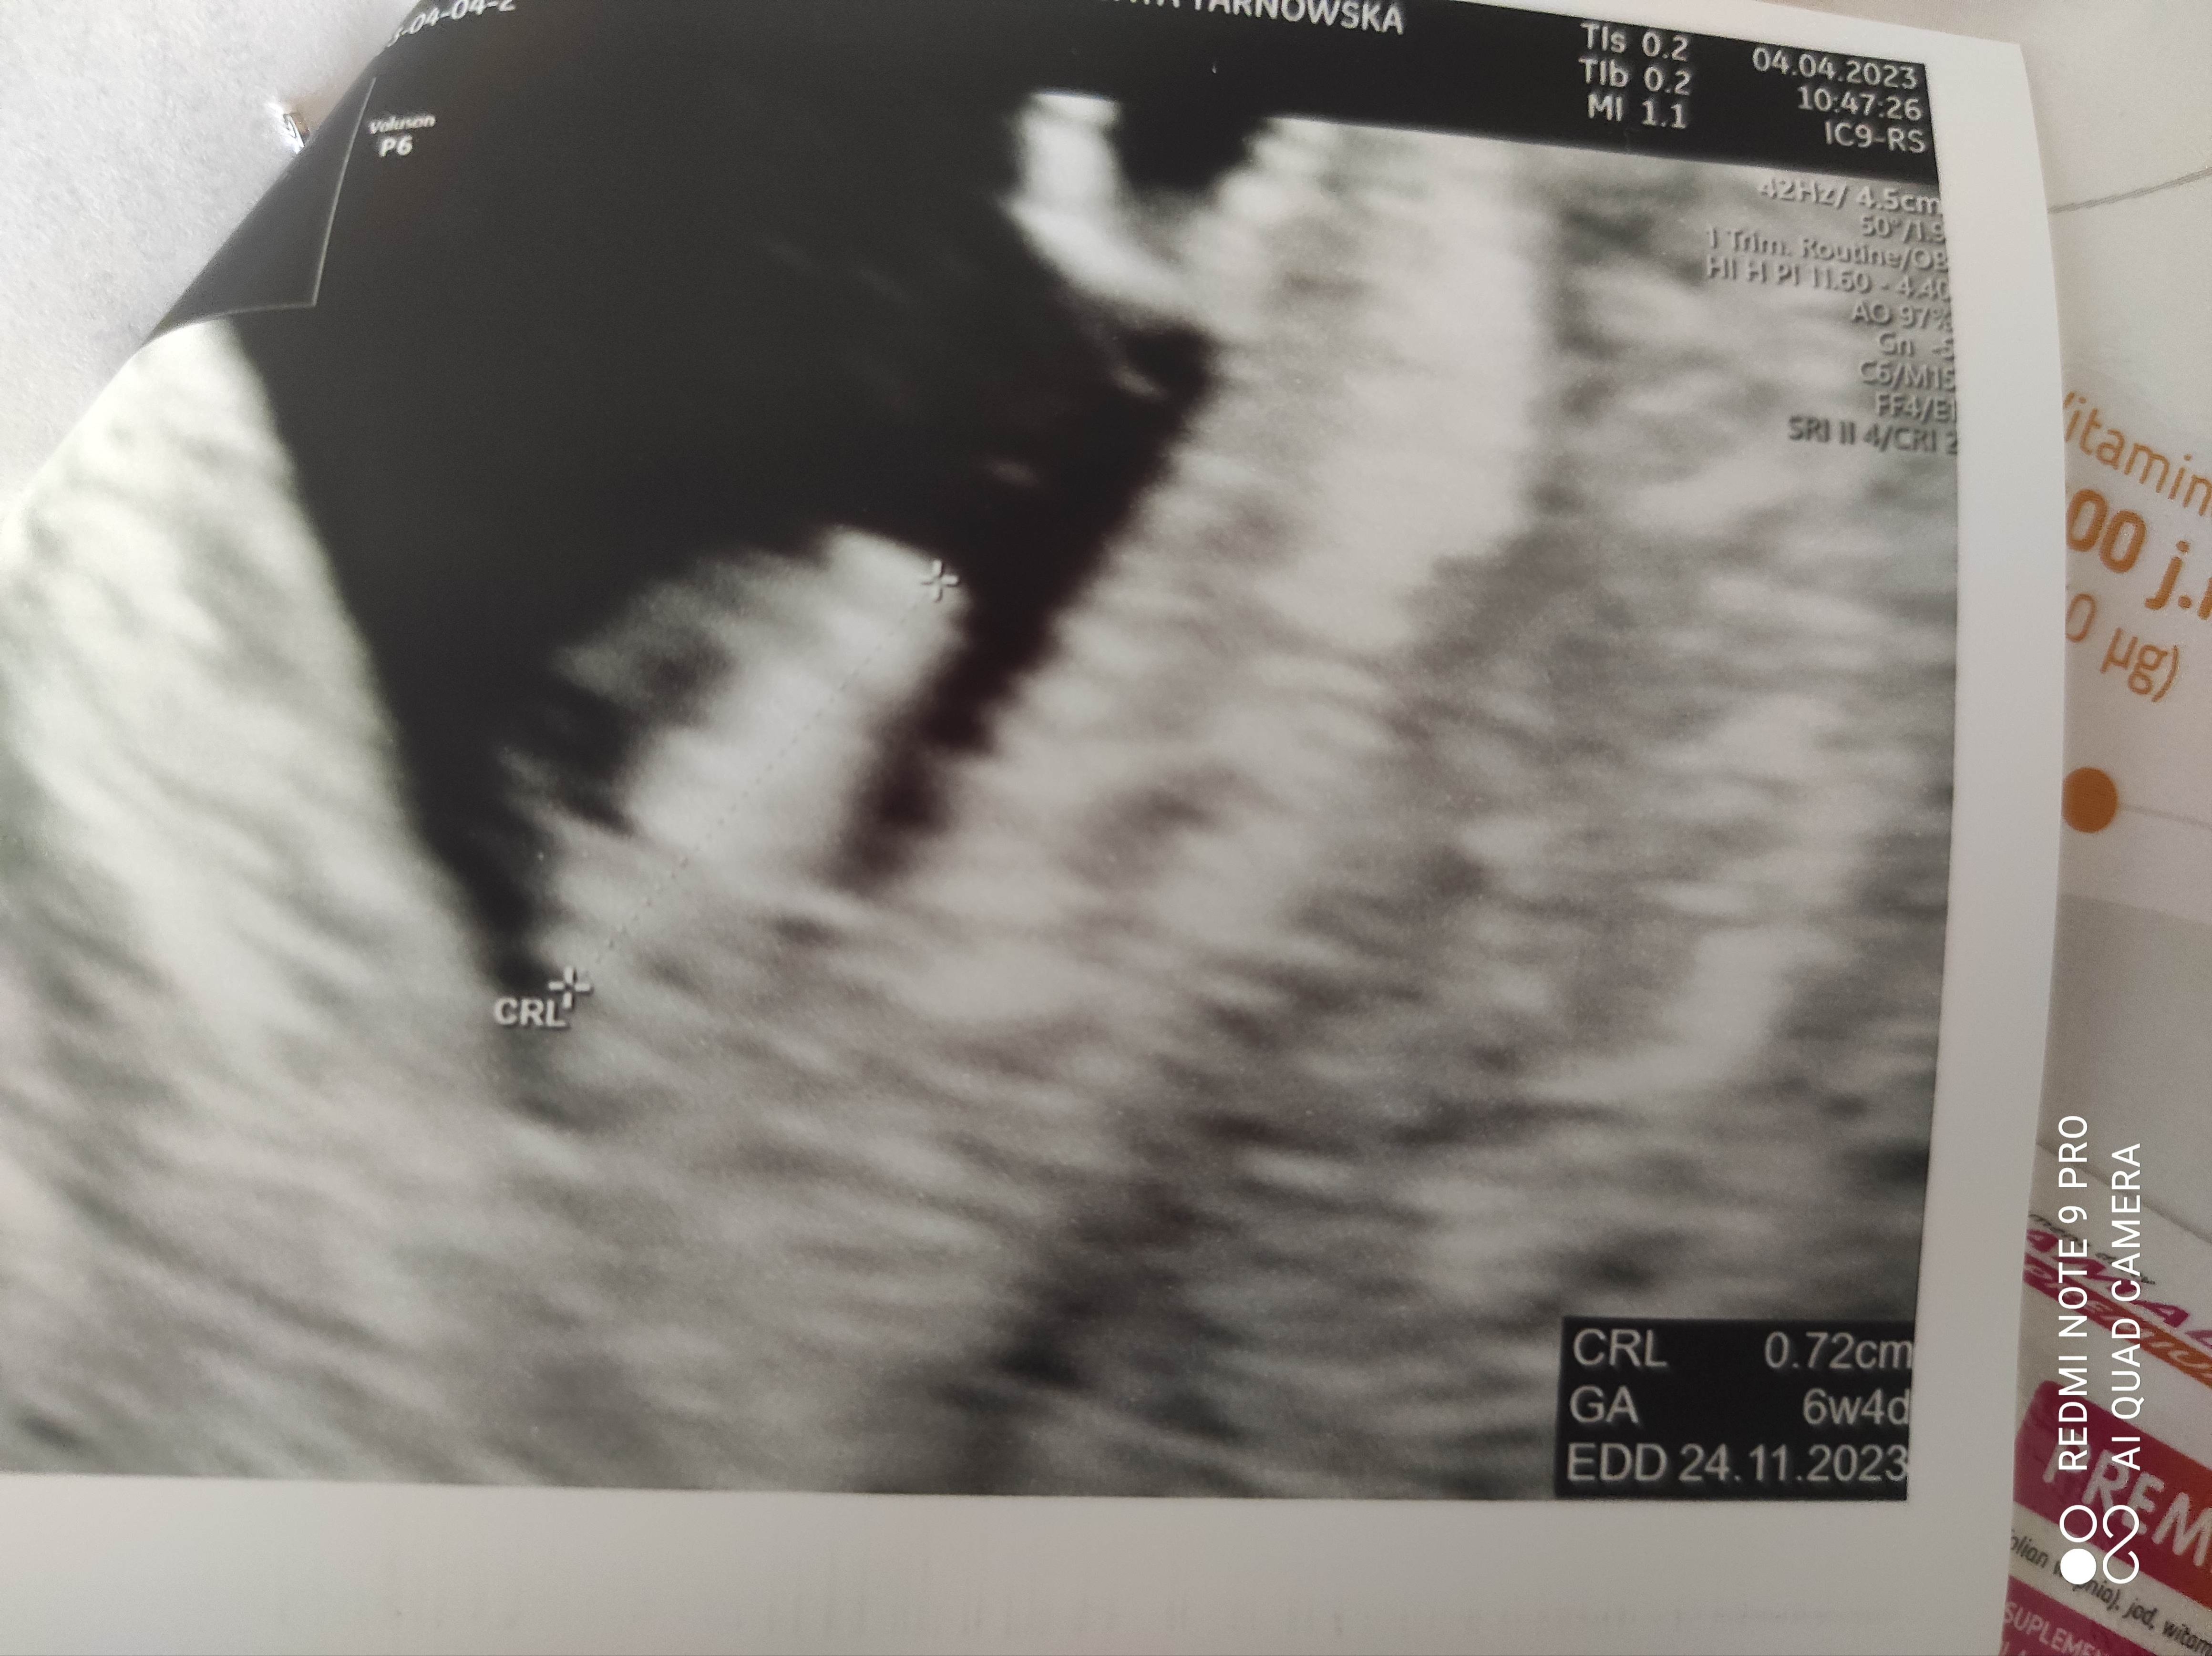

A czy jesteś pewna daty owulacji?Dziewczyny ja po pierwszej wizycie! Tak naprawdę nie wiem co myśleć, serduszko jest, bije, z USG 6+4, z okresu 7+3 więc martwi mnie ta rozbieżność.... Dodatkowo dostałam skierowanie NFZ na badania prenatalne a mam dopiero 27, z powodu chorób, naprawdę myślałam że dają dopiero po 35 roku, ale chciałam do innego miejsca i mam dylemat. Jeszcze mam dylemat co do prowadzenia ciąży, bo do niej poszłam prywatnie na samo potwierdzenie, a chciałam prowadzić u lekarza oddalonego o 80 km ode mnie z super prywatnym szpitalem, jednak okazało się że pani jest naprawdę kompetentna i dała mi to skierowanie, nie wiem czy nie zostać tutaj tylko wtedy musiałabym rodzić w tym szpitalu dziadowskim niedaleko mnie, eh. Mam dylemat straszny.

Co do rozbieżności- jeśli nie masz pewności kiedy była owulacja to może być taka różnica kilku dni.Dziewczyny ja po pierwszej wizycie! Tak naprawdę nie wiem co myśleć, serduszko jest, bije, z USG 6+4, z okresu 7+3 więc martwi mnie ta rozbieżność.... Dodatkowo dostałam skierowanie NFZ na badania prenatalne a mam dopiero 27, z powodu chorób, naprawdę myślałam że dają dopiero po 35 roku, ale chciałam do innego miejsca i mam dylemat. Jeszcze mam dylemat co do prowadzenia ciąży, bo do niej poszłam prywatnie na samo potwierdzenie, a chciałam prowadzić u lekarza oddalonego o 80 km ode mnie z super prywatnym szpitalem, jednak okazało się że pani jest naprawdę kompetentna i dała mi to skierowanie, nie wiem czy nie zostać tutaj tylko wtedy musiałabym rodzić w tym szpitalu dziadowskim niedaleko mnie, eh. Mam dylemat straszny.